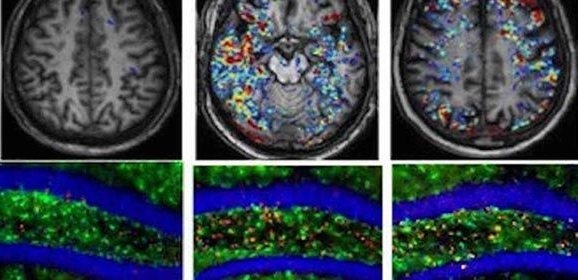

CIUDAD DE MÉXICO.- Nancy Ivette Arana de las Casas, catedrática del área de Posgrado en el Tecnológico Nacional de México (TecNM), encabeza una investigación de la actividad cerebral para determinar si las pausas en las actividades laborales disminuyen la carga mental que producen las nuevas formas de organización y producción.

La investigación de la catedrática del campus Ciudad Cuauhtémoc, en el estado de Chihuahua, se realiza con base en el proyecto Mejora de productividad intelectual mediante determinación de estados mentales con interfaz cerebro-computadora, y estudia el rendimiento laboral de distintos tipos de trabajadores, al igual que el agotamiento físico y mental que genera su entorno.

El estudio de Nancy Ivette Arana de las Casas plantea que el desgaste mental se presenta con mayor frecuencia en las estaciones de trabajo en comparación con la carga física, lo que afecta proporcionalmente al rendimiento laboral de cada individuo.

Se realizaron mediciones fisiológicas como la electroencefalografía (actividad eléctrica cerebral) y el comportamiento del ritmo cardiaco, para estudiar sus variaciones y determinar el aumento o disminución de los estímulos cerebrales.